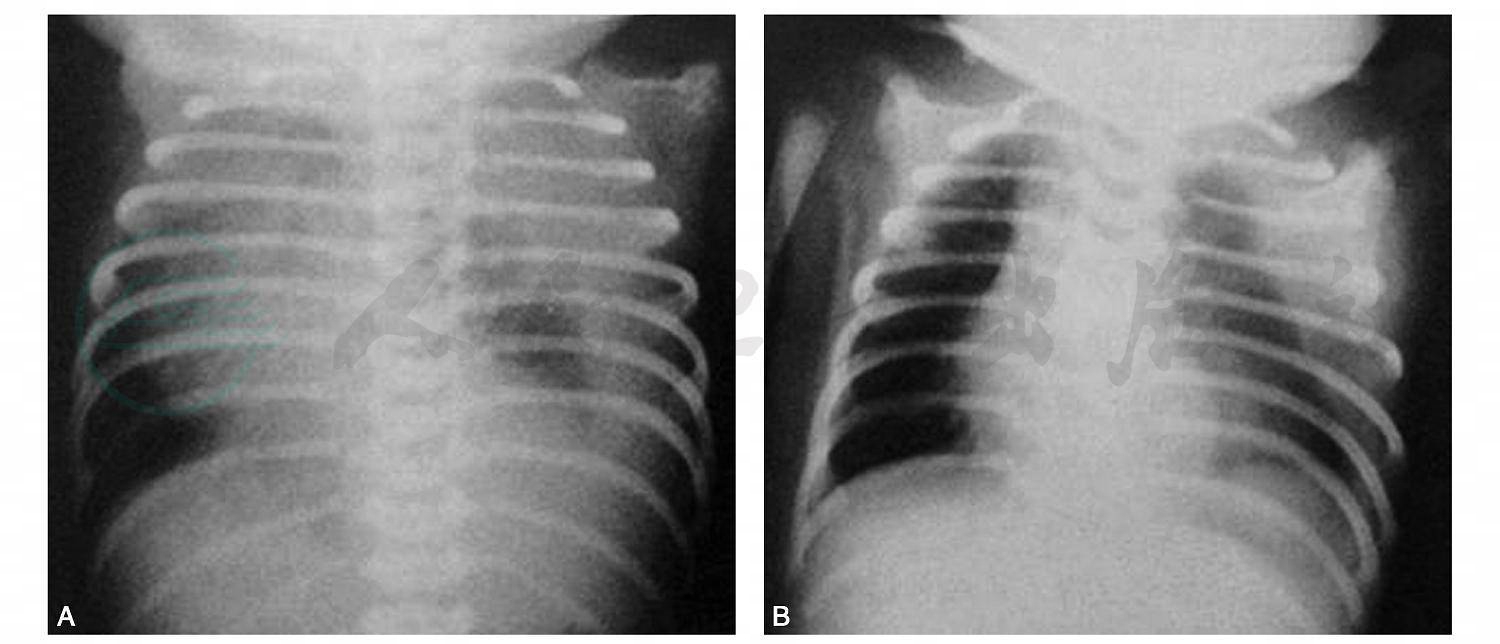

图2乳糜胸

男性,25小时,足月顺产,生后5小时出现气急、发绀。A.胸部正位片示左侧胸腔一片致密,肋间隙增宽,纵隔右移明显;B.抽出约300ml乳糜状胸水后复查,左侧胸壁有条状致密影,左肺内中带有斑片状密度增高影